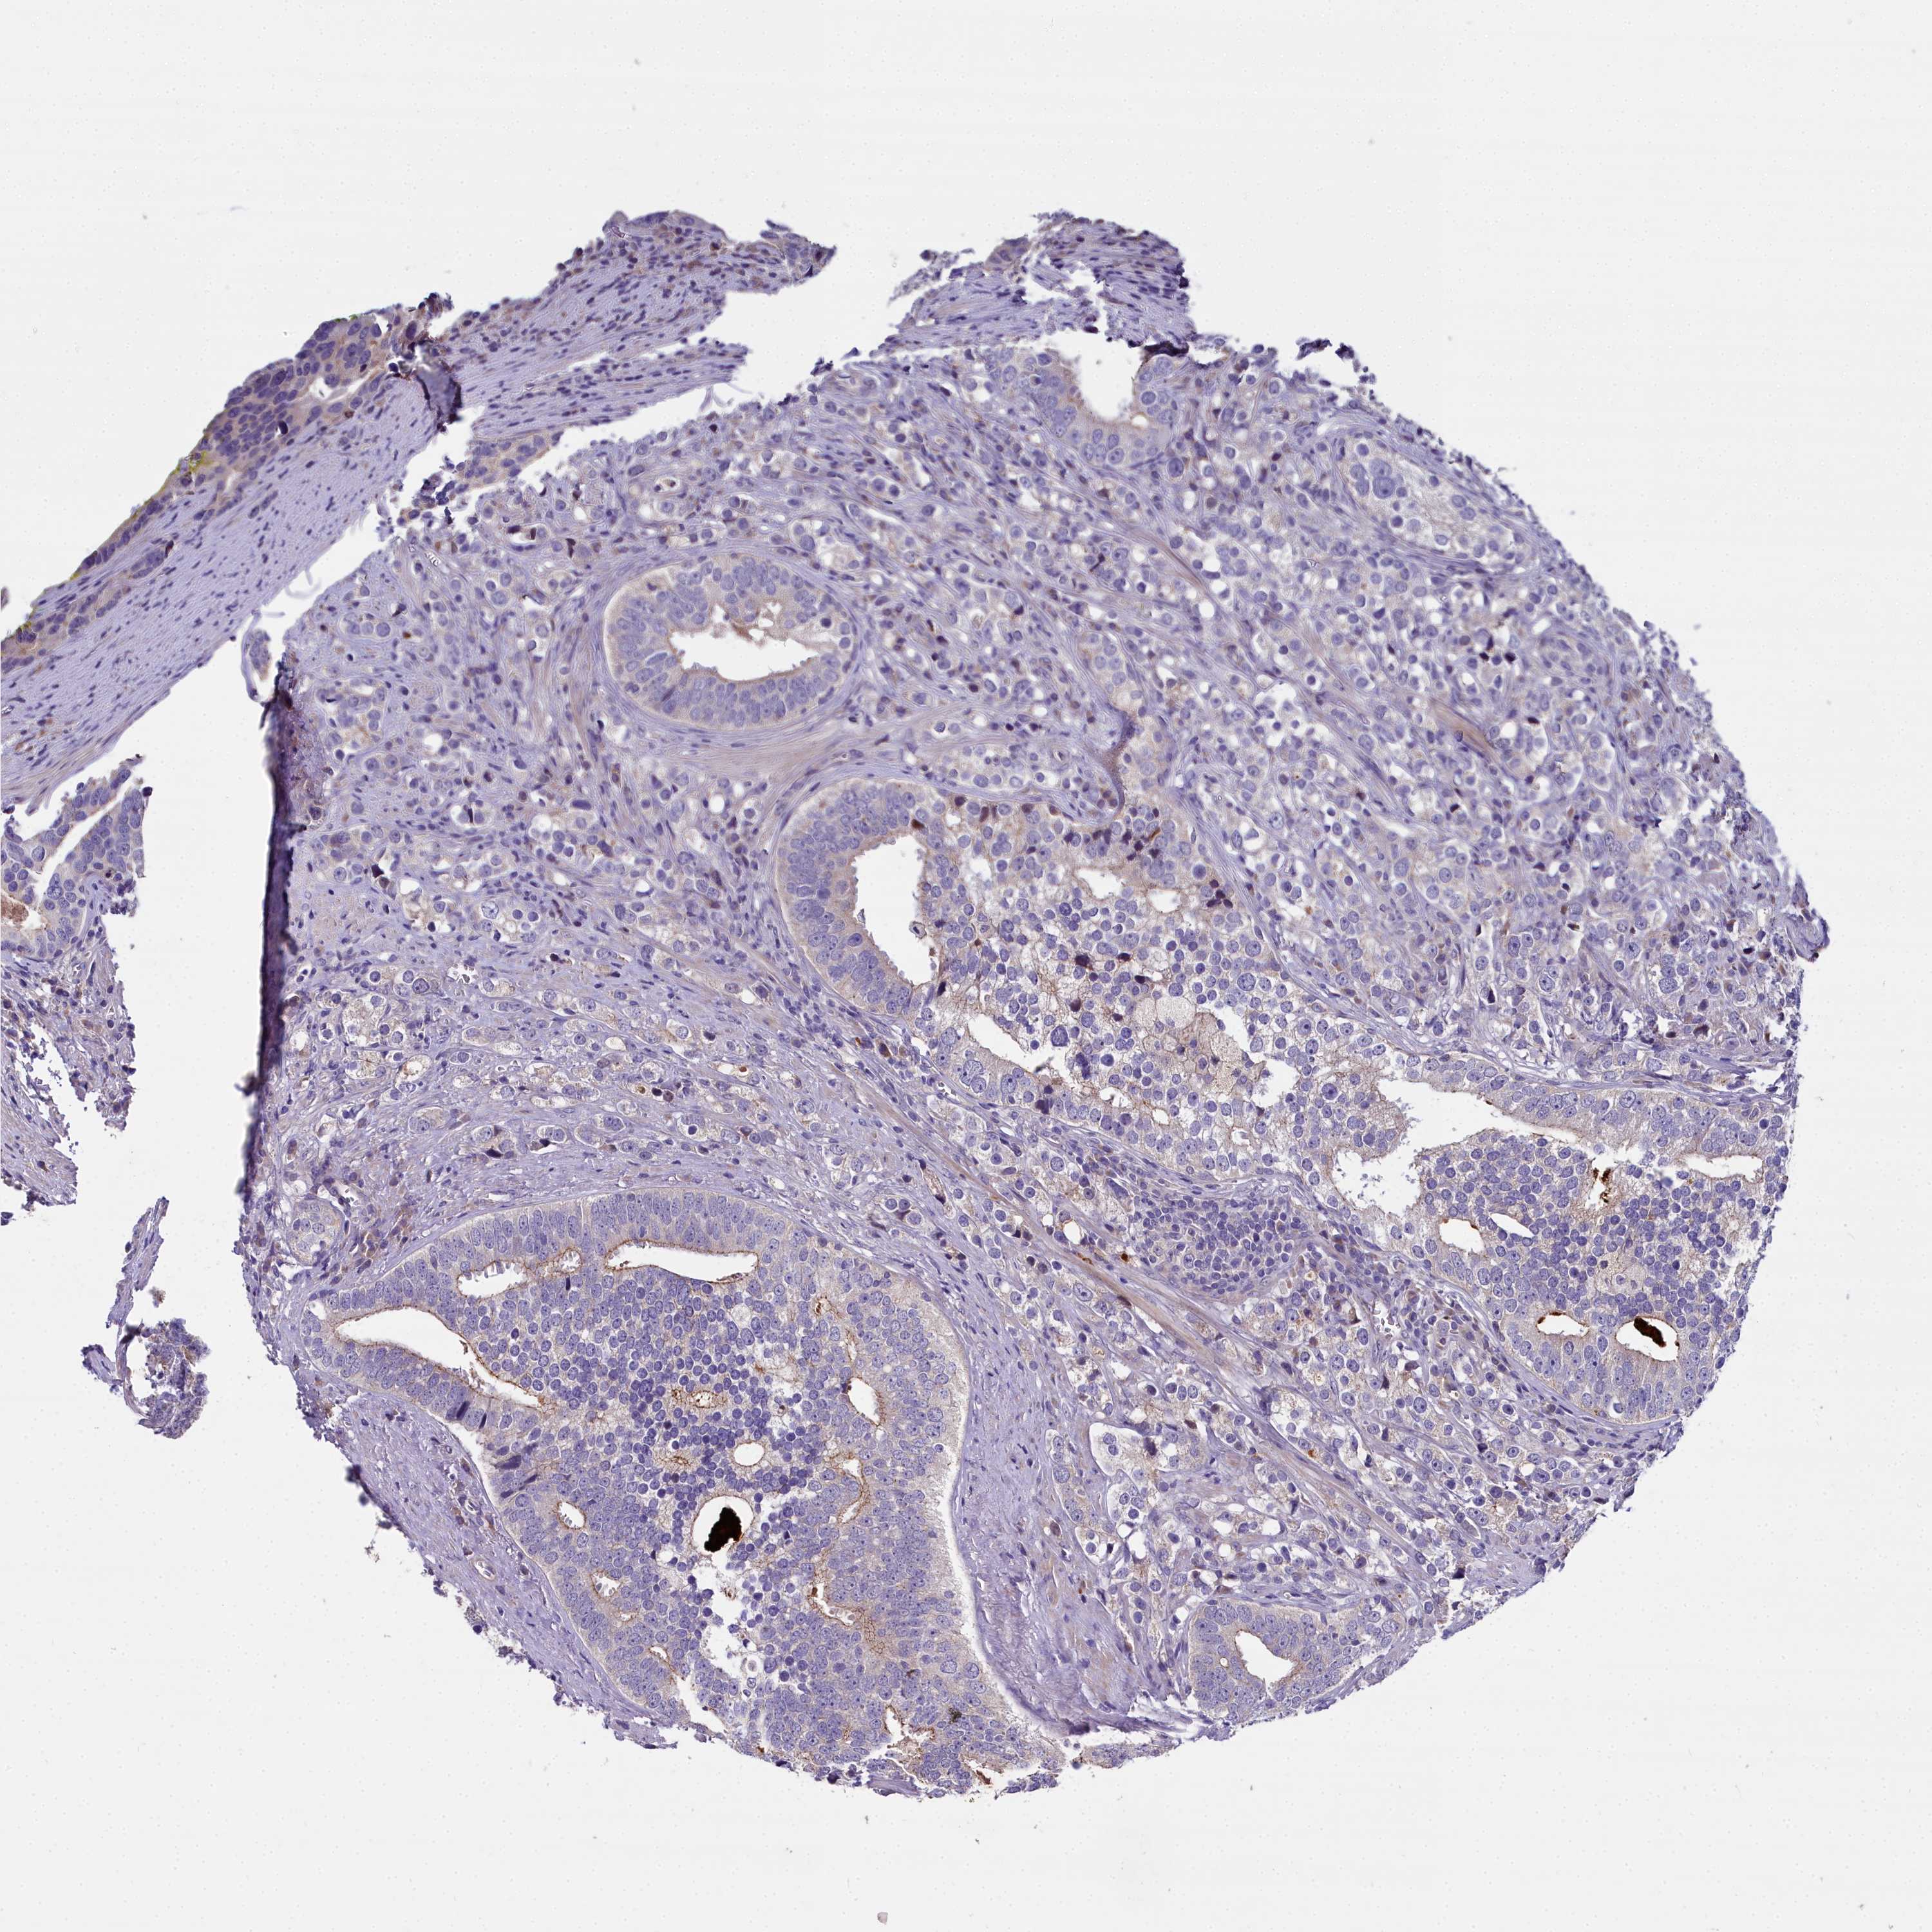

PROSTATE CANCER - Protein expressioni

A mouse-over function shows sample information and annotation data. Click on an image to view it in a full screen mode. Samples can be filtered based on level of antibody staining by selecting one or several of the following categories: high, medium, low and not detected. The assay and annotation is described here.

Note that samples used for immunohistochemistry by the Human Protein Atlas do not correspond to samples in the TCGA dataset.

Antibody stainingi

Antibody staining in the annotated cell types in the current human tissue is reported as not detected, low, medium, or high, based on conventional immunohistochemistry profiling in selected tissues. This score is based on the combination of the staining intensity and fraction of stained cells.

Each image is clickable and will lead to virtual microscopy that enables deeper exploration of all samples and also displays staining intensity scores, fraction scores and subcellular localization as well as patient and tissue information for each sample.

Antibody HPA043777

Staining

High

Medium

Low

Not detected

Intensity

Strong

Moderate

Weak

Negative

Quantity

>75%

75%-25%

<25%

None

Location

Nuclear

Cytoplasmic/membranous

Cytoplasmic/membranous,nuclear

Adenocarcinoma, NOS

Adenocarcinoma, High grade

Adenocarcinoma, Low grade